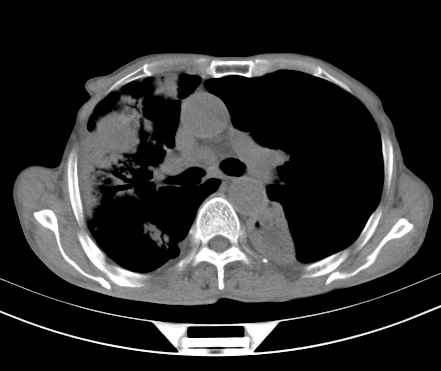

以下是引用gaoshengjiang在2008-5-30 19:53:00的发言:[br]右上叶可见大片实变影,其内可见充气支气管影及囊状影,右上叶尖端支气管走形区可见结节样影,左侧胸腔内可见胸腔胃影。纵隔淋巴结肿大。[br]考虑:1.右上肺阻塞性肺炎伴肺脓肿形成。支持转移所致。[br] 2.左侧胸腔胃。